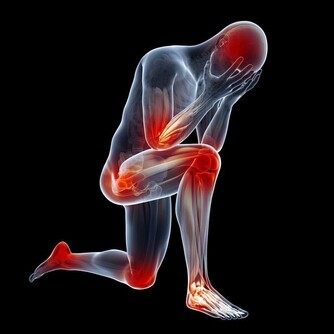

甲狀腺術後後遺症,手術需謹慎,切記!

我先從顯而易見的後遺症說起。

下面要說的後遺症,具有高度的隱秘性,你也許一輩子都注意不到,你術後的生活的改變。直到有一天,你忽然發現,原來你的很多其他的病痛都和它有關係,或者就是有它而起的,此時的它就更像藏在你身體裡的魔鬼了。來無影,去無踪,卻無時無處不發揮作用。

甲狀腺癌術後的後遺症主要的就是這些了,這些後遺症也是最有代表性的,80%的患者都會遇到。區別只是程度不同而已。我更是一項不拉的全佔了。